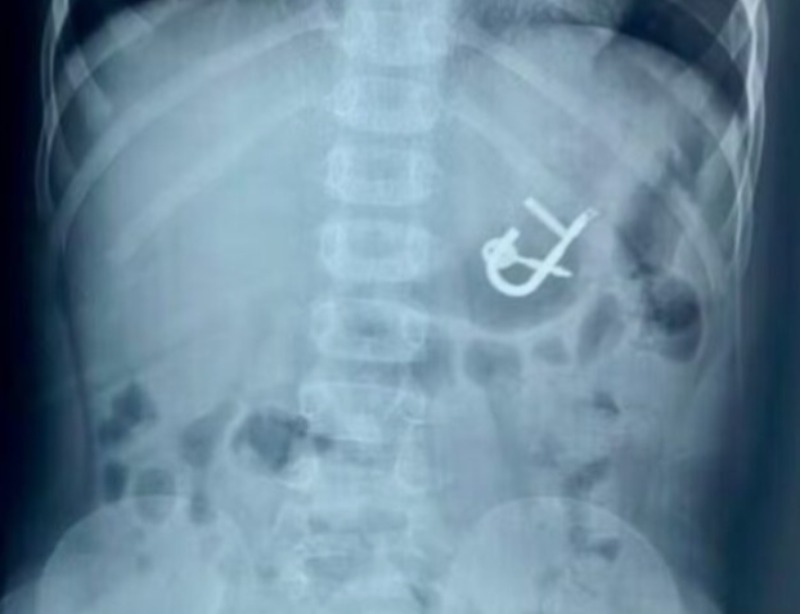

“Quando eu cheguei no raio x, já dava para ver que o cadeado estava no estômago. A nossa maior preocupação era o tempo de passar e esse cadeado progredir para o intestino, porque provavelmente ocasionaria uma obstrução intestinal, e realmente teria que ser cirúrgico. Então, rapidamente fomos para o bloco cirúrgico para fazer a anestesia da criança. O cirurgião Nairton estava a postos, se durante a retirada houvesse lesão no esôfago e precisasse de cirurgia de urgência. Felizmente, deu tudo certo, nós realizamos a retirada em aproximadamente 20 minutos”, explicou.

Uma criança de quatro anos engoliu um cadeado com as chaves em Cedro, no Sertão de Pernambuco. O menino deu entrada no último sábado (10) no Hospital Regional Inácio de Sá, em Salgueiro. O objeto foi retirado com sucesso, no mesmo dia, por meio de endoscopia digestiva, e o paciente já teve alta médica.

O menino ingeriu o objeto por acidente. “Ele estava brincando com o cadeado na boca, as chaves estavam presas ao cadeado. Ele estava tentando retirar a chave com a boca, aparentemente, se desequilibrou, caiu para trás e acabou engolindo um cadeado de aproximadamente cinco centímetros, que estava fechado com a chave”, esclareceu.